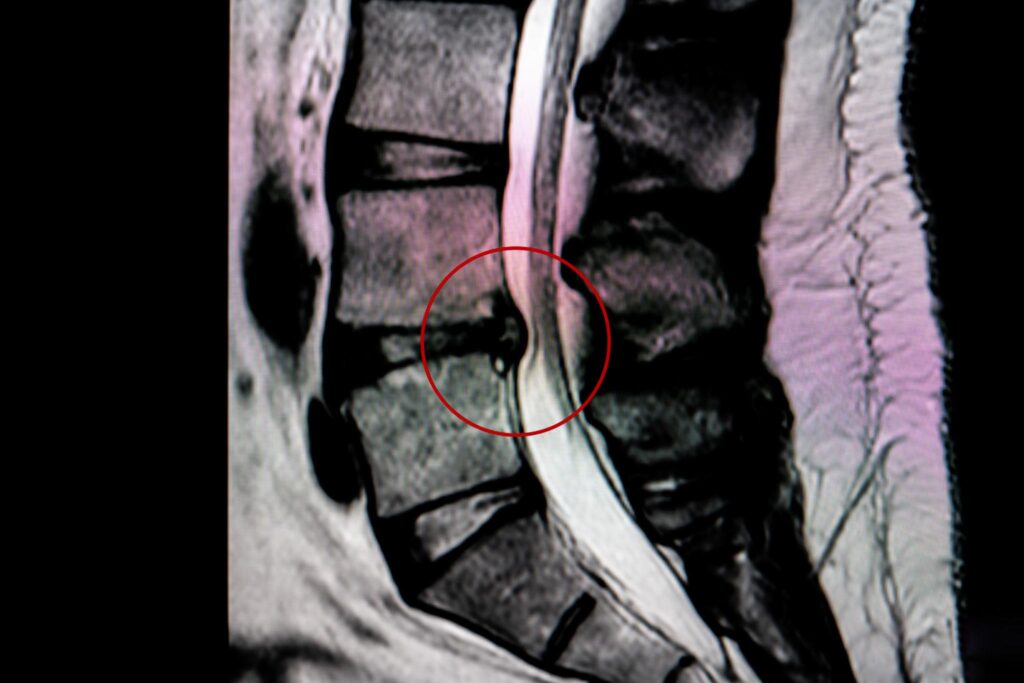

ファシア(筋膜)の一部

筋膜は筋肉や骨、神経を包み、全身をつないでいる結合組織です。

この筋膜が乾燥したり、動きが悪くなったり、かたまった状態になると、動いたときに一部に負担が集中します。その結果、痛みとして感じることがあります。

しかし、こうした質の変化は通常のMRIではほとんど確認できません。